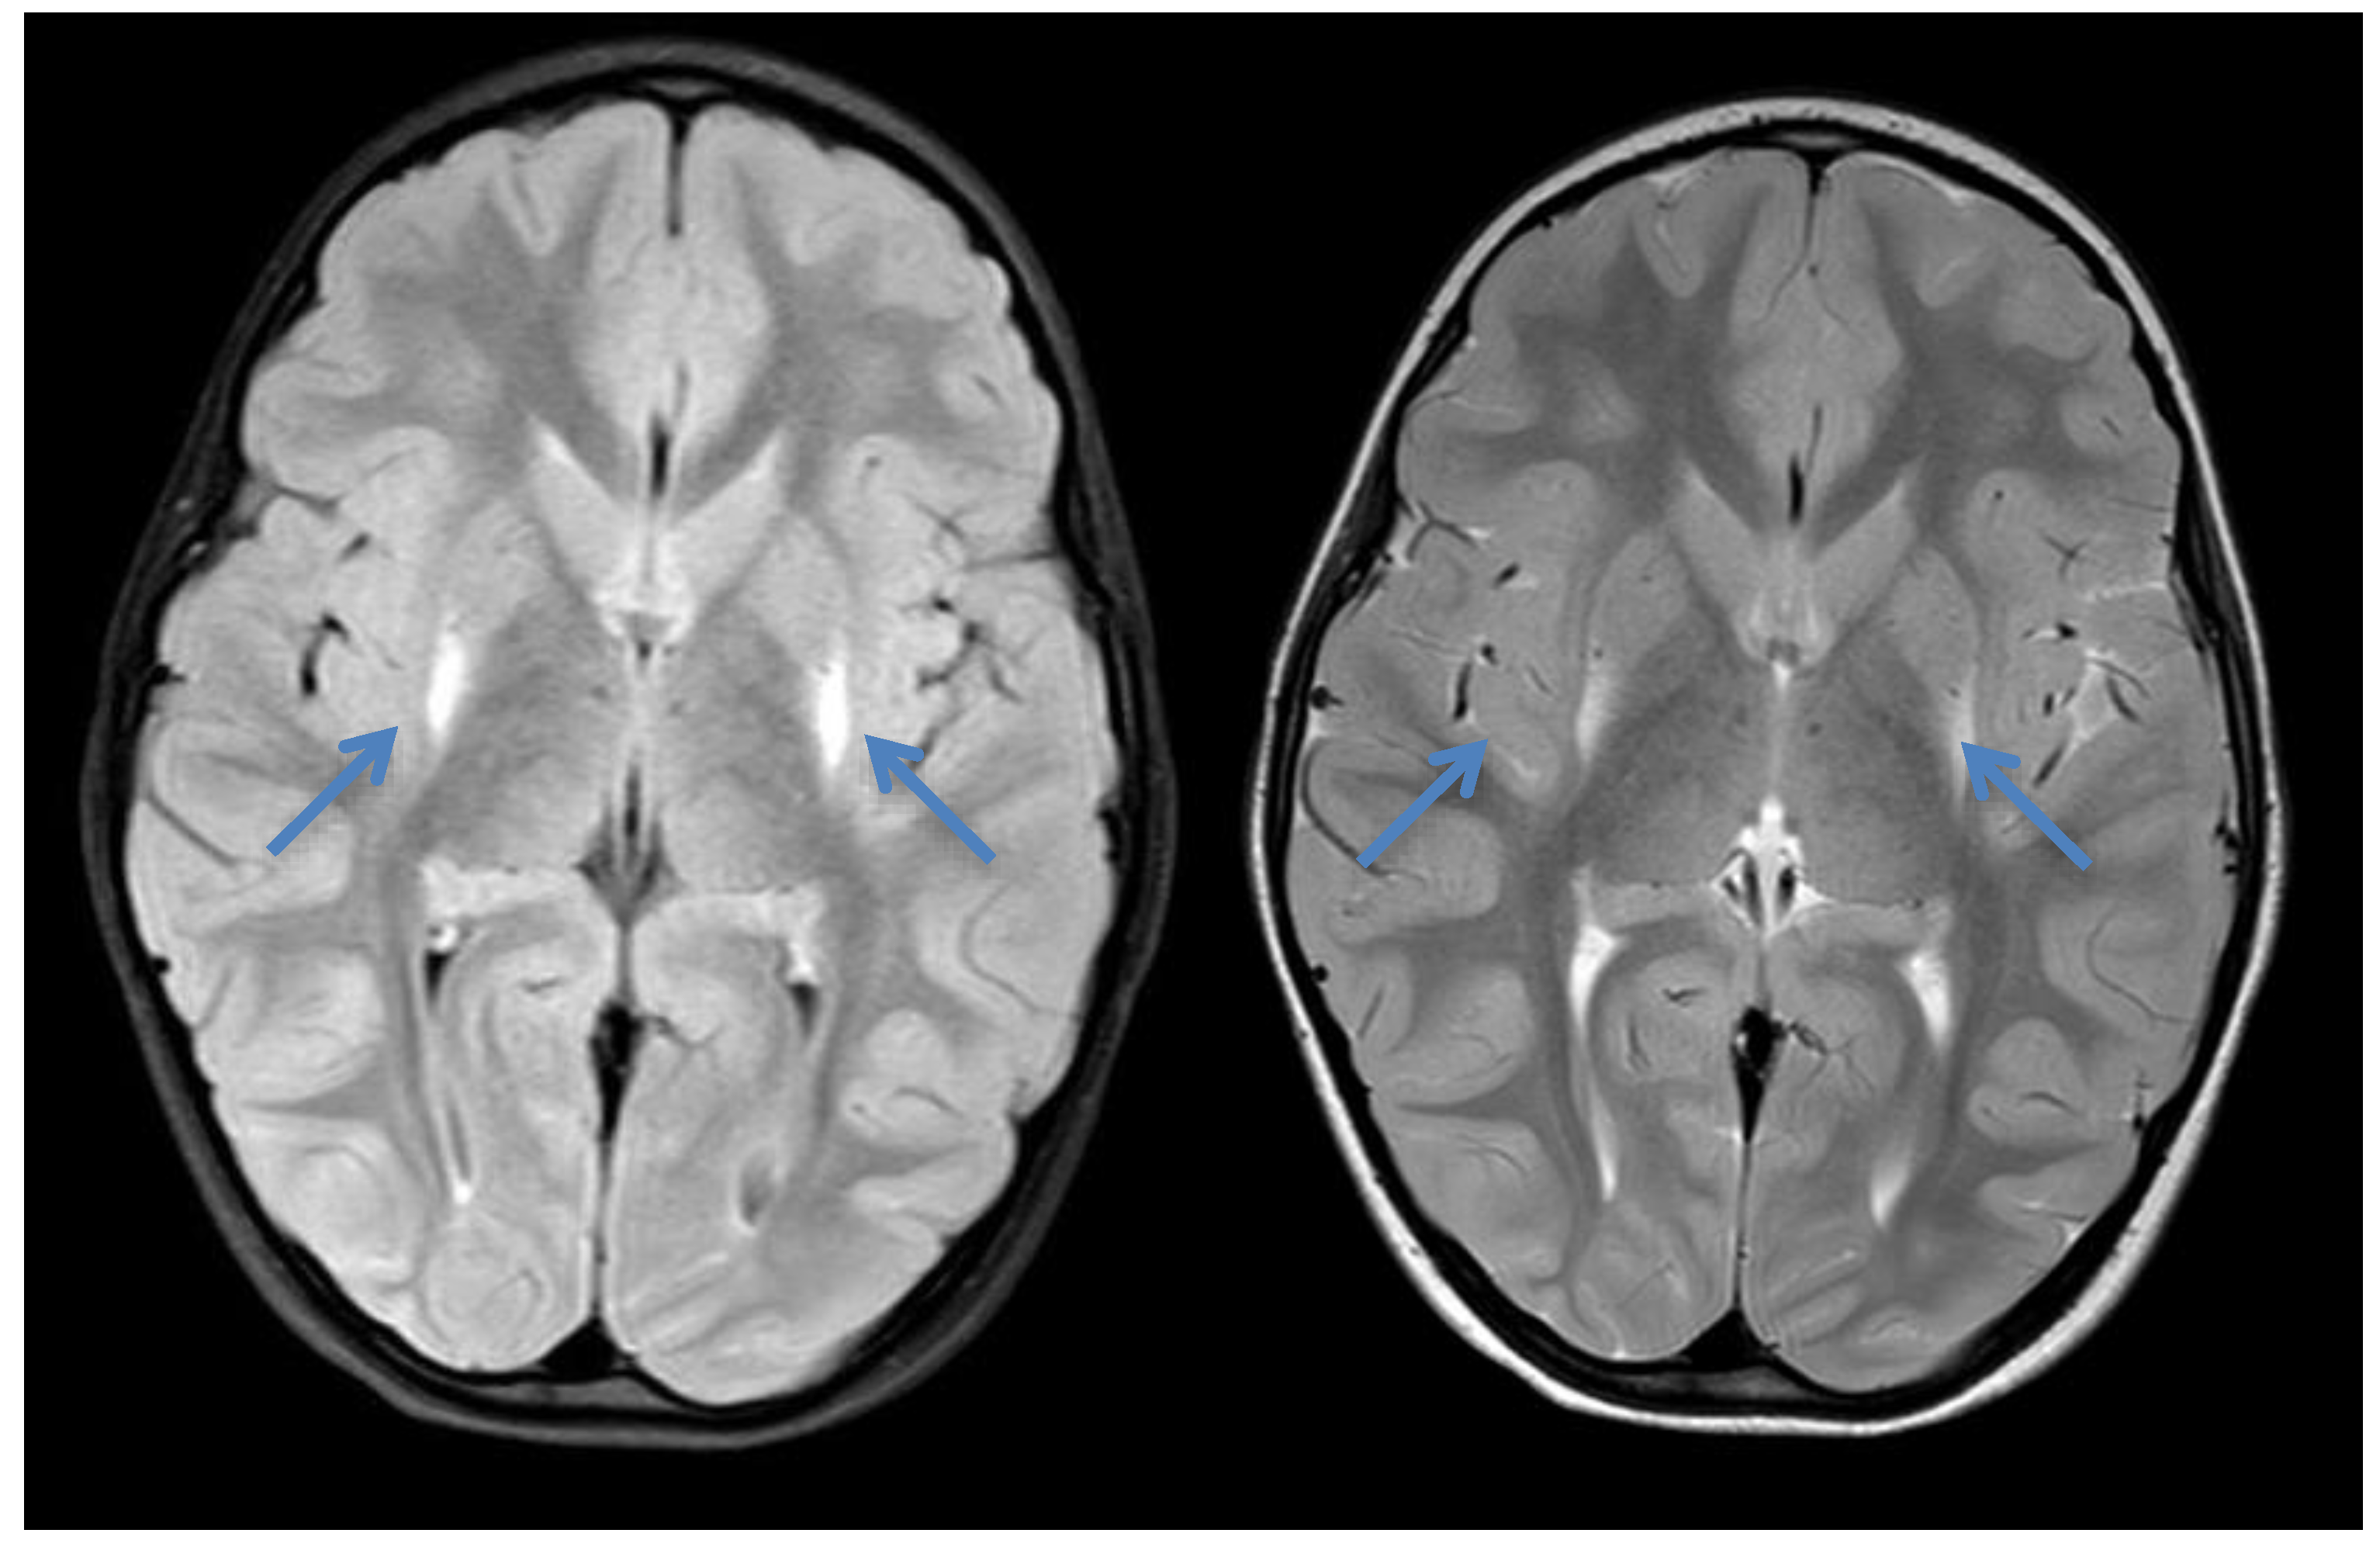

2.1. Case 1

2.2. Case 2

2.3. Case 3

2.4. Case 4